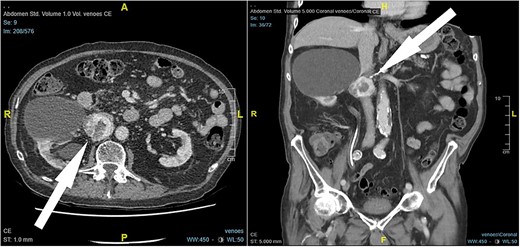

An 87-year-old male Caucasian patient with a history of cardiac co-morbidities, diabetes mellitus type 2, and chronic kidney disease stage 4 was referred to our hospital for clinical evaluation and a non-contrast abdominal–pelvic CT scan because of right side pain with a history of kidney stone disease, with recurrent ureteral stones. The CT scan showed a small distal ureteral stone on the right side without the need for surgical intervention. Incidentally, he had a retroperitoneal mass (4.4 × 4 × 4 cm) posterior to the inferior vena cava, with compression on the inferior vena cava and the right renal artery (Fig. 1). Our radiologist classified this unexpected incidental finding as a possible neuroendocrine tumor, with the recommendation to perform a DOTATE-PET/CT scan. The DOTATE-PET/CT showed a sizeable retrocaval mass with edge-accentuated radionuclide storage, compatible with a paraganglioma or a lymph node metastasis of a neuroendocrine tumor (Fig. 2). The ultimate etiology remained unclear, despite the radiological scans. Our blood tests showed a normal level of hormones in the blood and urine, excluding hormonally active tumors. The only noticeable value in the blood was the elevated creatinine as a part of the chronic kidney disease. One of our assumptions was that the tumor compression on the renal artery impacts the patient’s kidney function. The patient reported no remarkable symptoms.

CT scan findings, 4.5 × 4 × 4 cm right retroperitoneal mass posterior to the inferior vena cava, with compression on the inferior vena cava and the right renal artery (arrow).